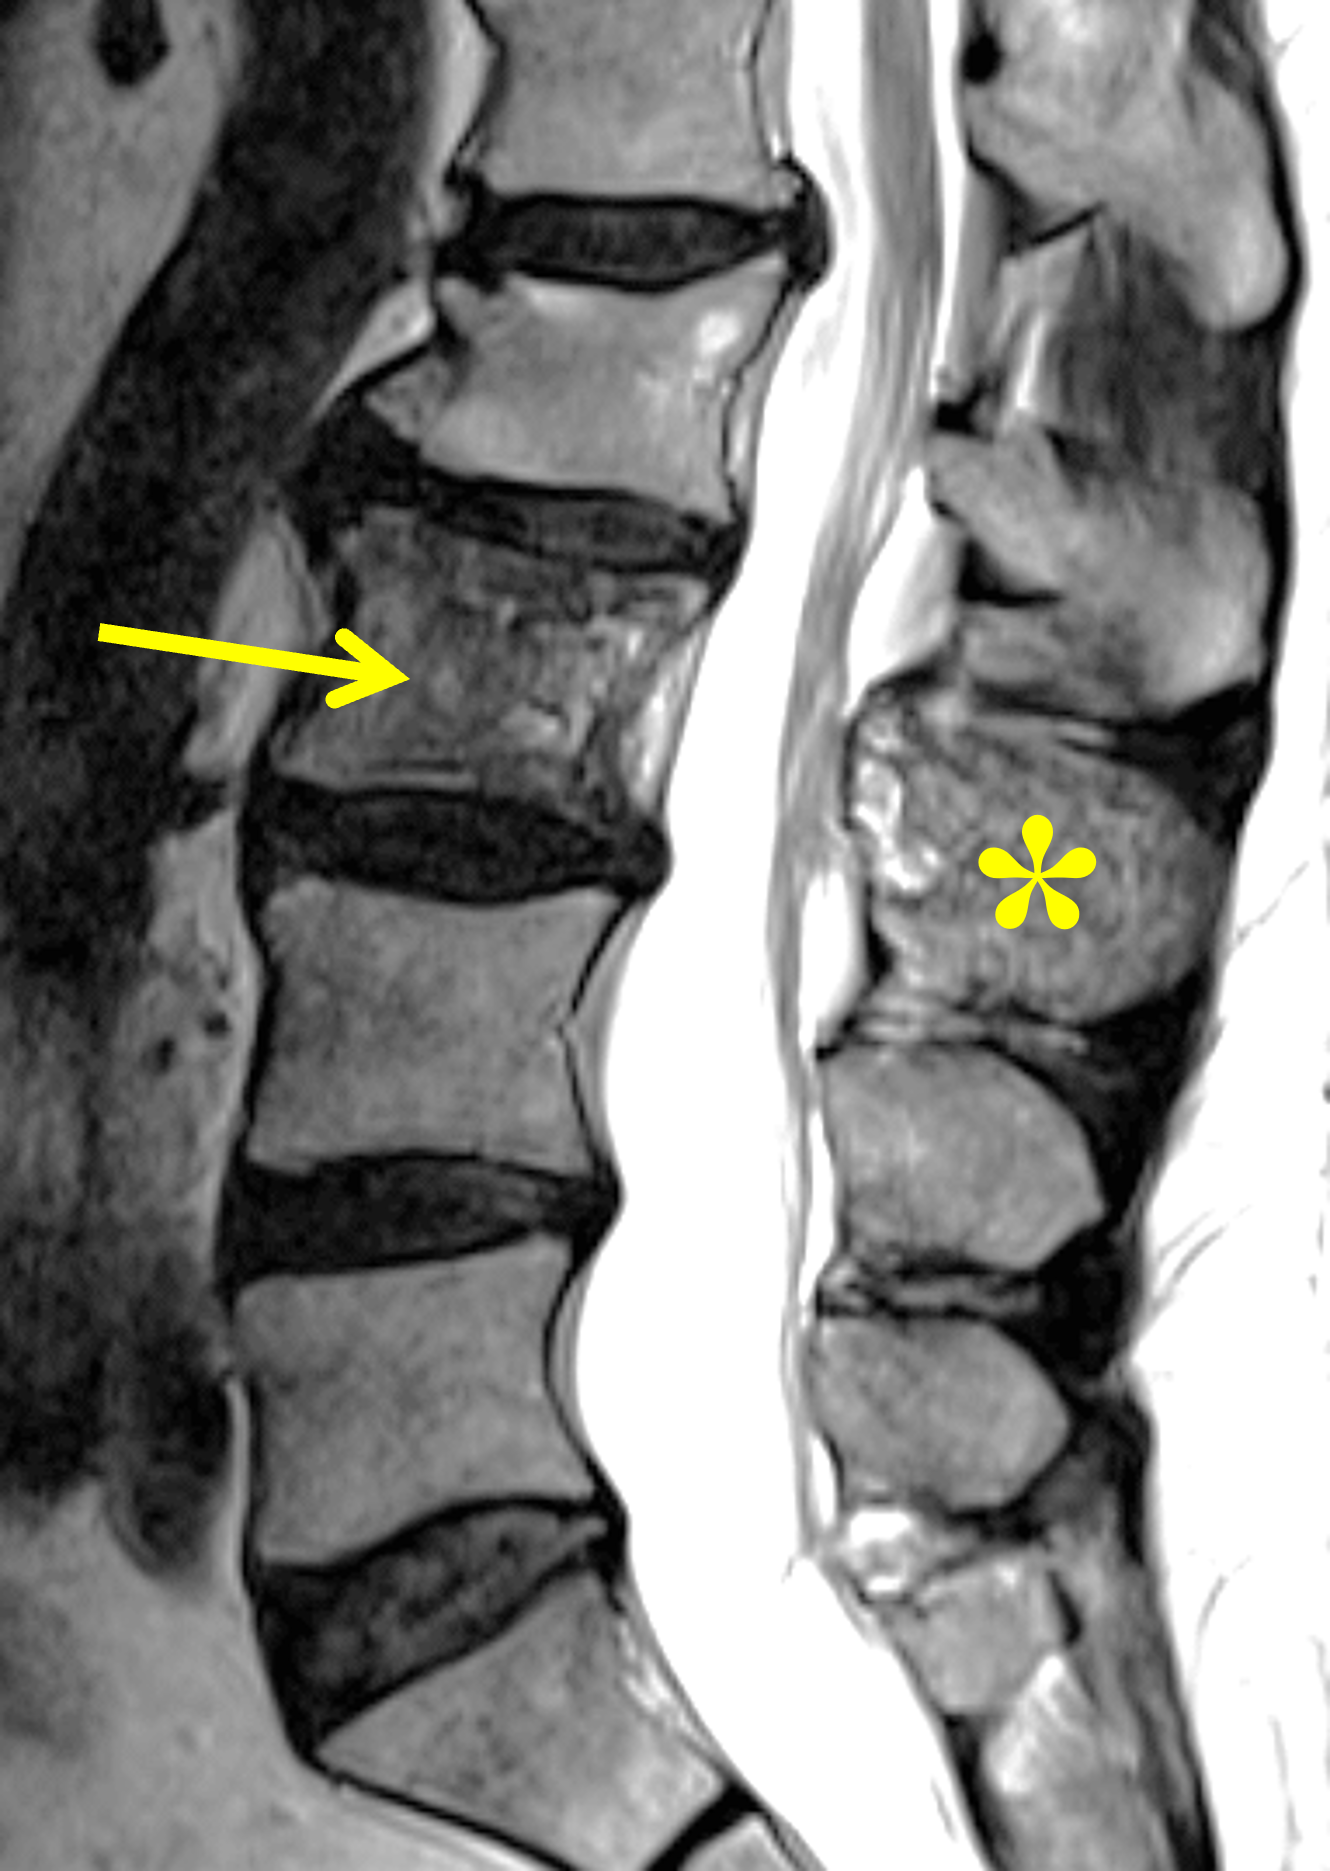

Figure 5. Mixed phase Paget disease of L3, MRI pattern 2. (5A) Sagittal T2-weighted image shows heterogeneous marrow (arrow) in the L3 vertebral body, with regions of both mildly increased and decreased signal intensity. Note the involvement of the spinous process (asterisk), which is characteristic of Paget disease involving the spine. (5B) Sagittal T1-weighted image shows small foci of preserved marrow fat (arrow), a finding that distinguishes Paget disease from malignant infiltration. Note the thickened, vertically-oriented trabeculae. (5C) Sagittal STIR image shows only minimally hyperintense marrow signal (arrow). (5D) Sagitally-reconstructed CT image shows thick, coarse trabeculae in the vertebral body (arrow) and spinous process (asterisk), which can be seen in both Paget disease and hemangioma. The bone is subtly enlarged, but thickened cortex is not present. Because of diagnostic uncertainty, percutaneous biopsy was performed, confirming Paget disease. A healed, benign compression fracture involves the superior endplate of L2.